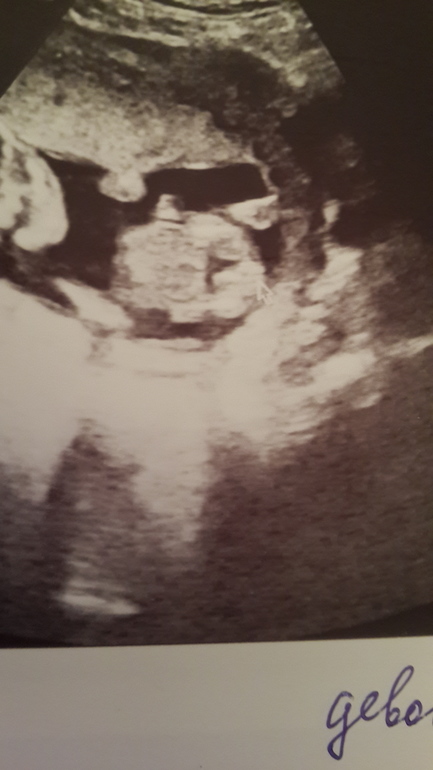

Я чувствую всеми фибрами души, что будет мальчулька и жду его собственно. И на фото узи я чётко вижу яйки))) врач ржёт, говорит, к окулисту направлю, если не отстанешь. Вот фото первое, вид со стороны попки, слева ножка, справа согнутая ножка, ребёнок на спине чуть завалившись на бок, между ножек ведь есть округлость указанная стрелкой!

Второе фото это срез поперёк и стрелка указывает на конкретные яички и писюлю!!!! А она пишет девочка.

а вот дочка на сроке 21 неделя. Вид со стороны попки, одна ножка согнута